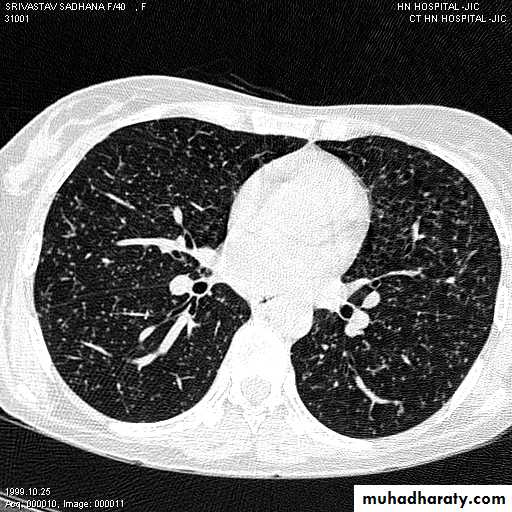

2-CT scan: indications:

• Assessment of trauma and emergency conditions.• assessment of masses( primary & secondary).

• Diagnosis Of interstitial disease.(HRCT...High resolution CT )

• guided procedures.

• CT angiography in suspected pulmonary embolism.

mediastinal window bone window lung window